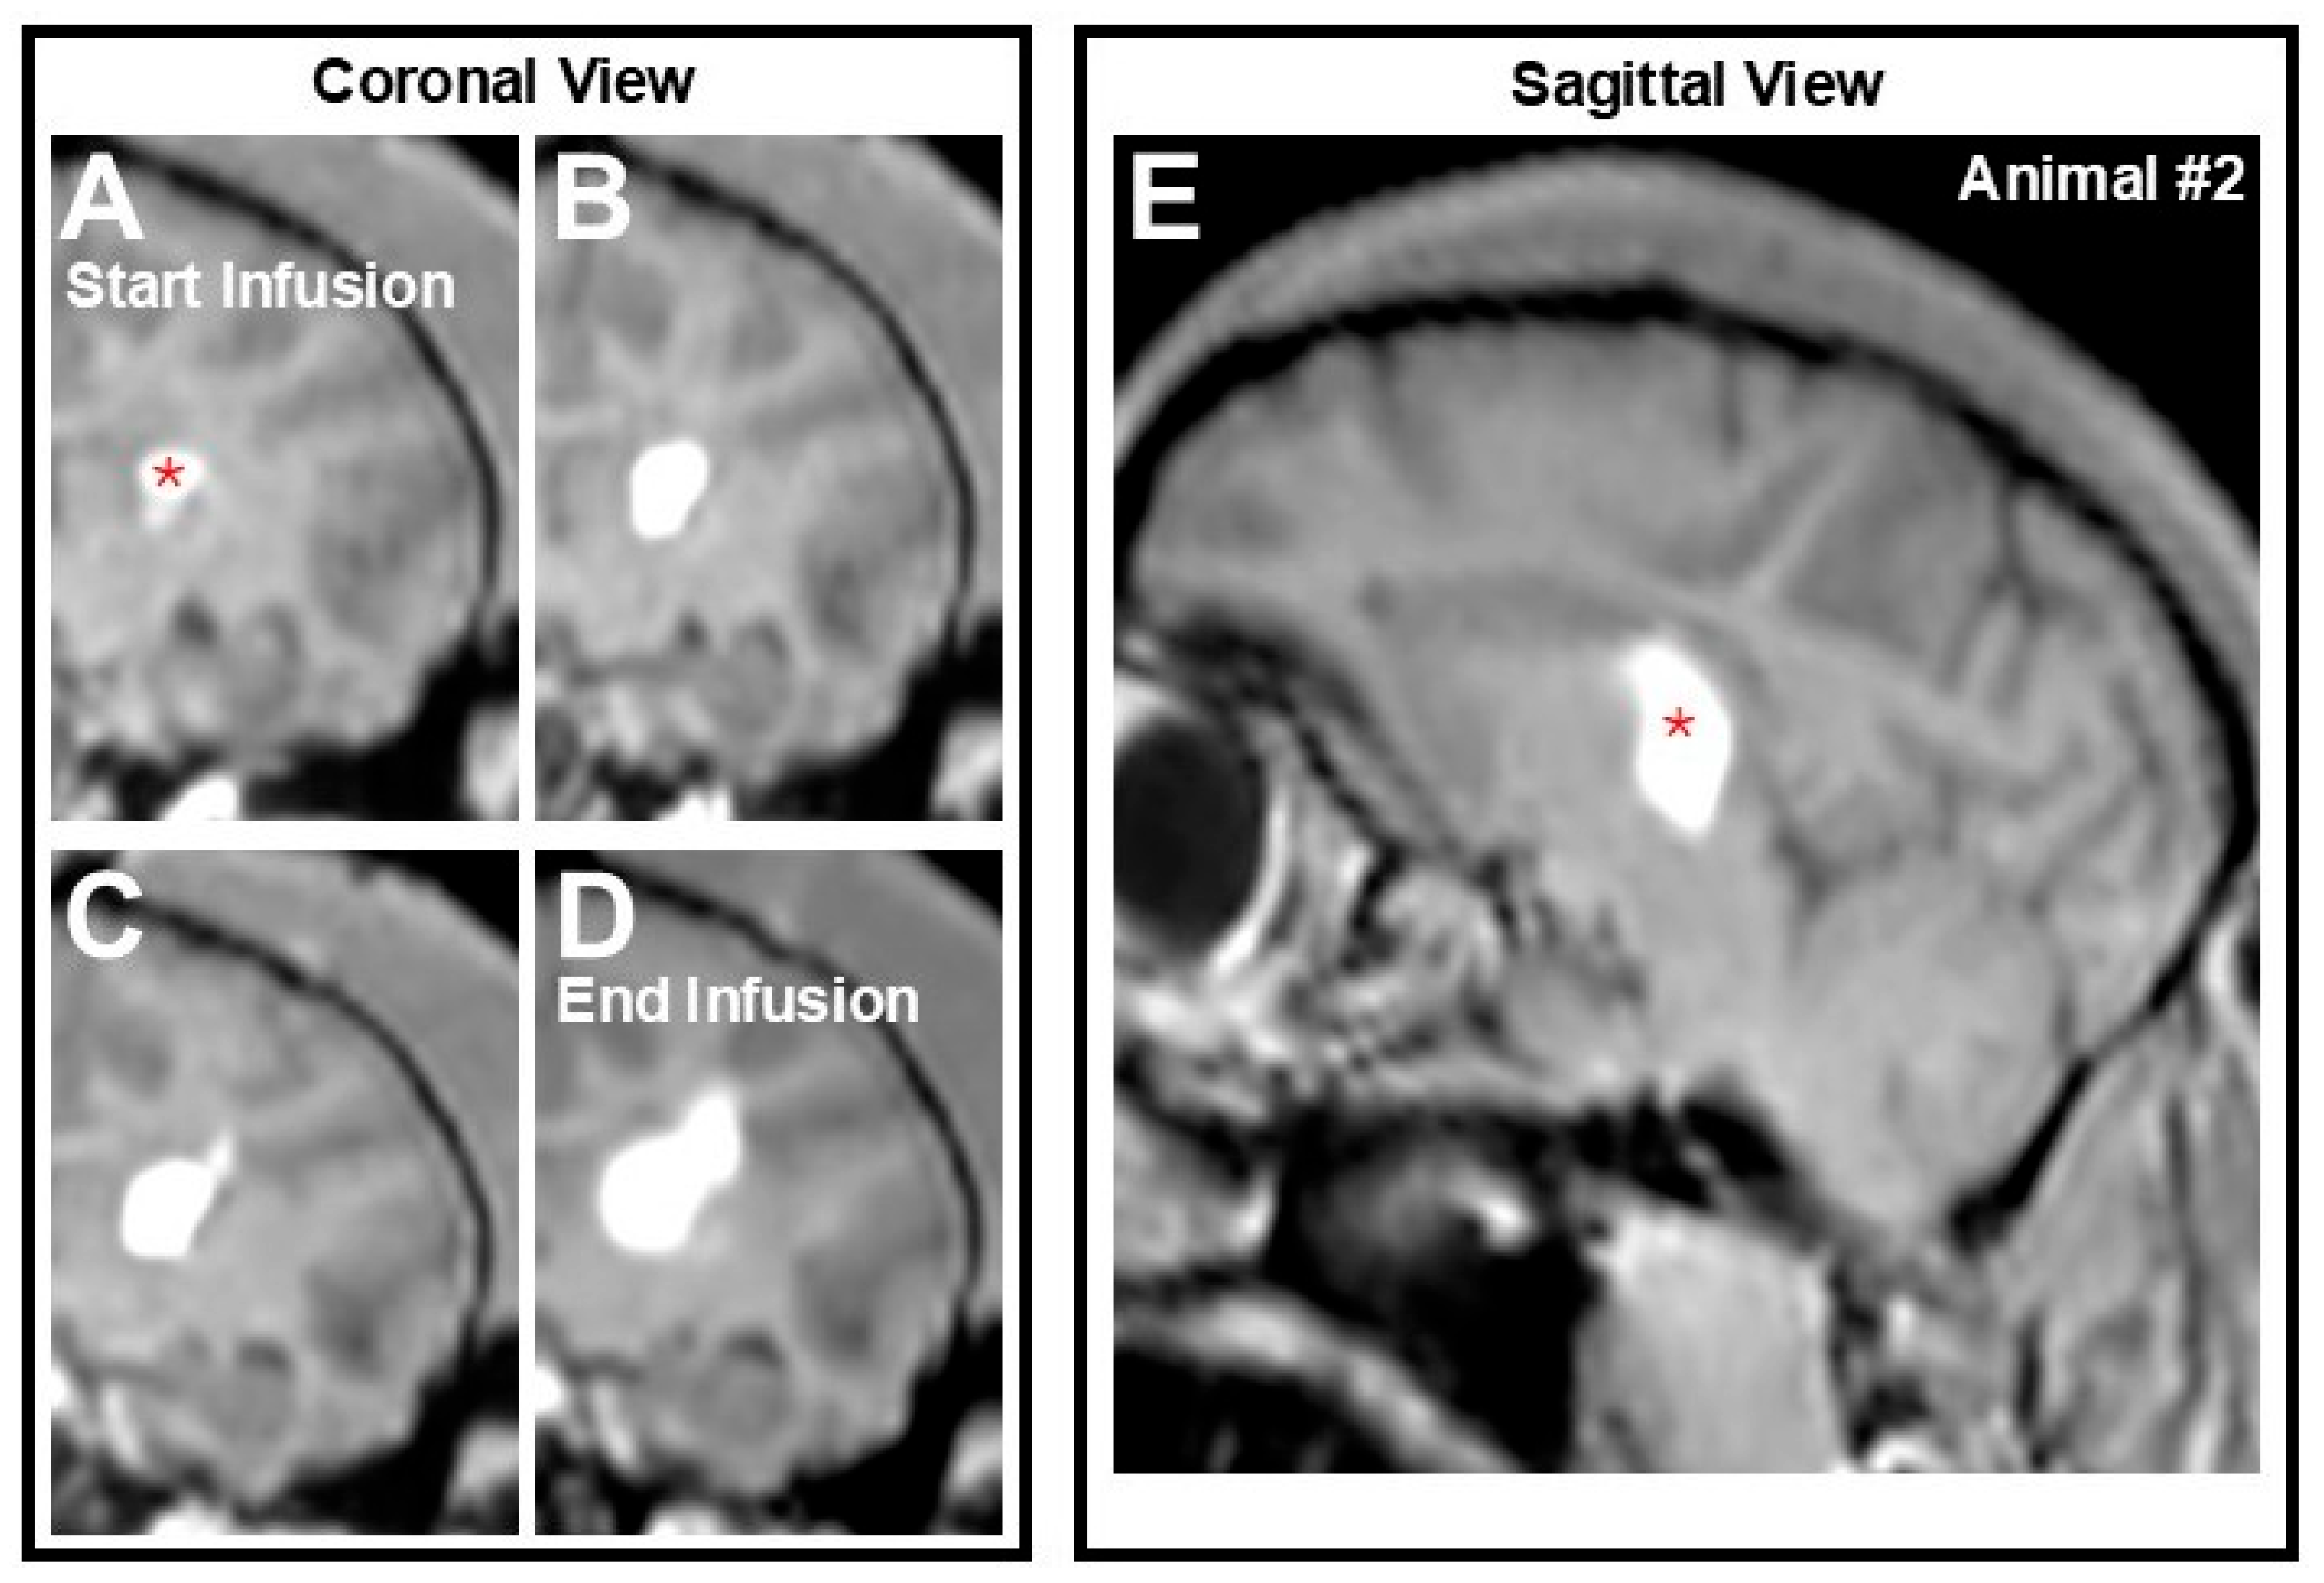

2.4. MRI-Guided Intracerebral Infusion